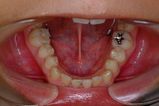

健康な小臼歯を抜いていません

矯正前                 矯正後

治療前 の 下アゴ です 動く矢印治療後 の 下アゴ です